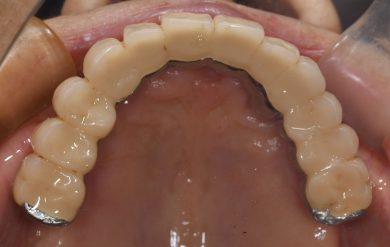

インプラント症例 術後18年 上顎無歯顎 オペ時72歳 現在90歳 上顎オールオン6

この方は術後10カ月で治療が完了しました。歯周病予防処置とあわせて計18回のご来院です。インプラント治療に関しては、10回です。

インプラント6本 サイナスリフト2ヵ所 オールオン6 仮歯 総費用約350万

術後18年 下顎臼歯は当初から使えるまで使ってインプラントにしようと話してましたが、今もなんでも咬めるということですので、90歳の今このまま使っていただいています。今後次の治療になる時は、訪問診療ですね。

18年後の補綴。クラシカルですが、十分機能しています。